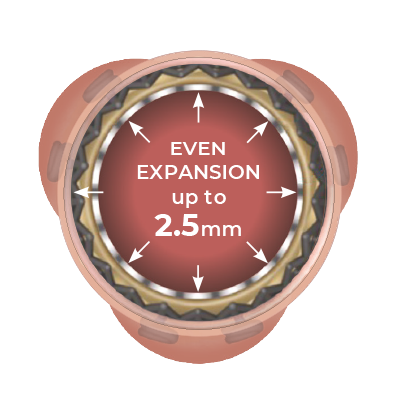

Designed for the future: the ideal docking station for Valve-in-Valve

Perceval Plus is a valve designed for the future. Not only is it durable,9 but it also gives patients even broader treatment options for their future. Its exclusive stent design allows even circumferential expansion to accommodate future transcatheter valves, making Perceval Plus ViV friendly by design. Thanks to its unique features, all patients eligible for biological AVR may benefit from a Perceval Plus implant.**12,13

Even circumferential expansion

The inflow ring can be evenly and circumferentially expanded up to 2.5mm above its nominal size, which allows for hemodynamic advantages and greater compatibility with TAVI models and sizes.

Minimized risk of coronary obstruction

Perceval Plus leaflets remain open when a TAVI is deployed inside it. The sinusoidal struts and the open leaflets create a space between the coronary ostia and the leaflets themselves wich is preserved even after the TAVI deployment.

Minimized risk of sinus sequestration

By design, the Perceval Plus leaflets, when open, do not touch the STJ, thus avoiding sinus sequestration.